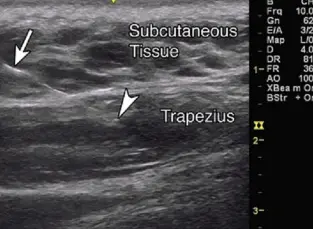

Ultrasound Guided Dry Needling(USGDN)

A magic treatment where USG guides needles to the root cause of pain and takes the patient to full activity levels. It is useful in all pains, either alone or after a block.